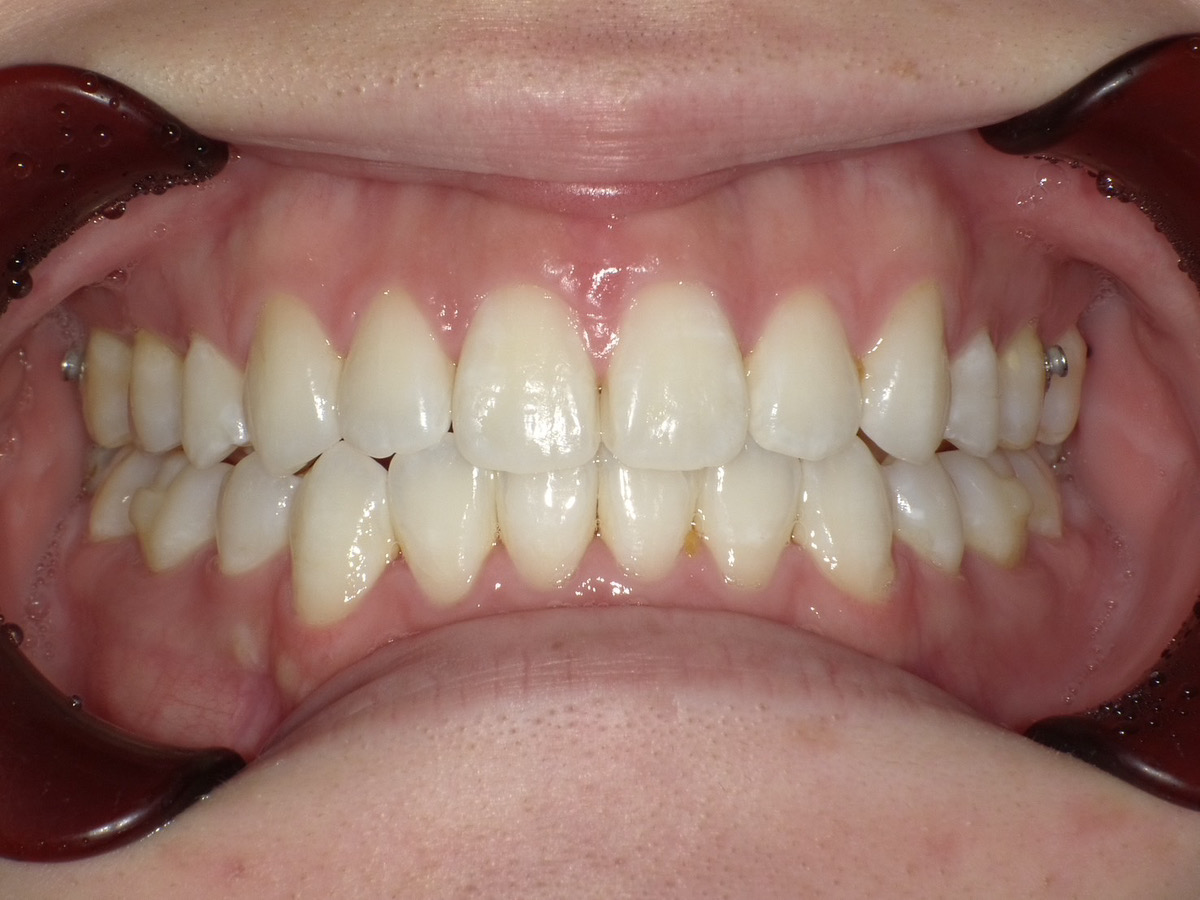

症例③

症例3_治療前 症例3_治療後

治療方法 マウスピース矯正

治療期間 1年8ヶ月

治療総額 850,000円

特記事項 抜歯なし

リスク・副作用 治療の初期段階では痛みや不快感が生じやすくなりますが、1週間前後で慣れます